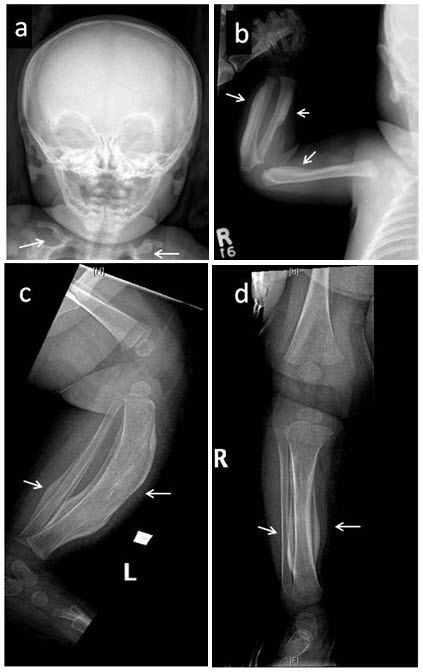

Figure 1. . Skeletal survey in a female age five weeks with the defining COL1A1 p.

圖1:對(duì)一名五周齡女性進(jìn)行的骨骼調(diào)查,該女性具有明確的 COL1A1 p.Arg1014Cys 致病性變異,其右脛骨出現(xiàn)疼痛性腫脹。注意廣泛參與 (a) 涉及下頜骨和鎖骨的對(duì)稱雙側(cè)骨膜反應(yīng); (b) 肱骨、橈骨近端軸和尺骨遠(yuǎn)端軸的不對(duì)稱受累; 和 (c,d) 脛骨和腓骨。箭頭指向顯著的骨膜下增厚和彎曲。 還注意到髂骨、股骨、脛骨和左腓骨的不對(duì)稱反應(yīng)(未顯示)。 癥狀在發(fā)作后一個(gè)月內(nèi)消失。